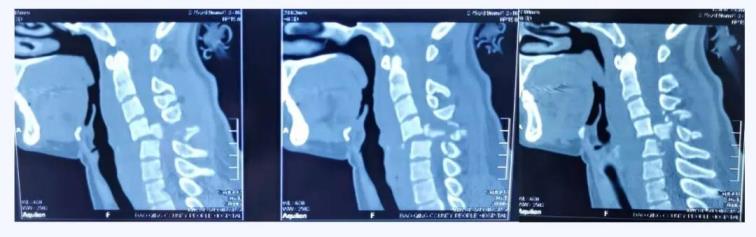

術(shù)前CT